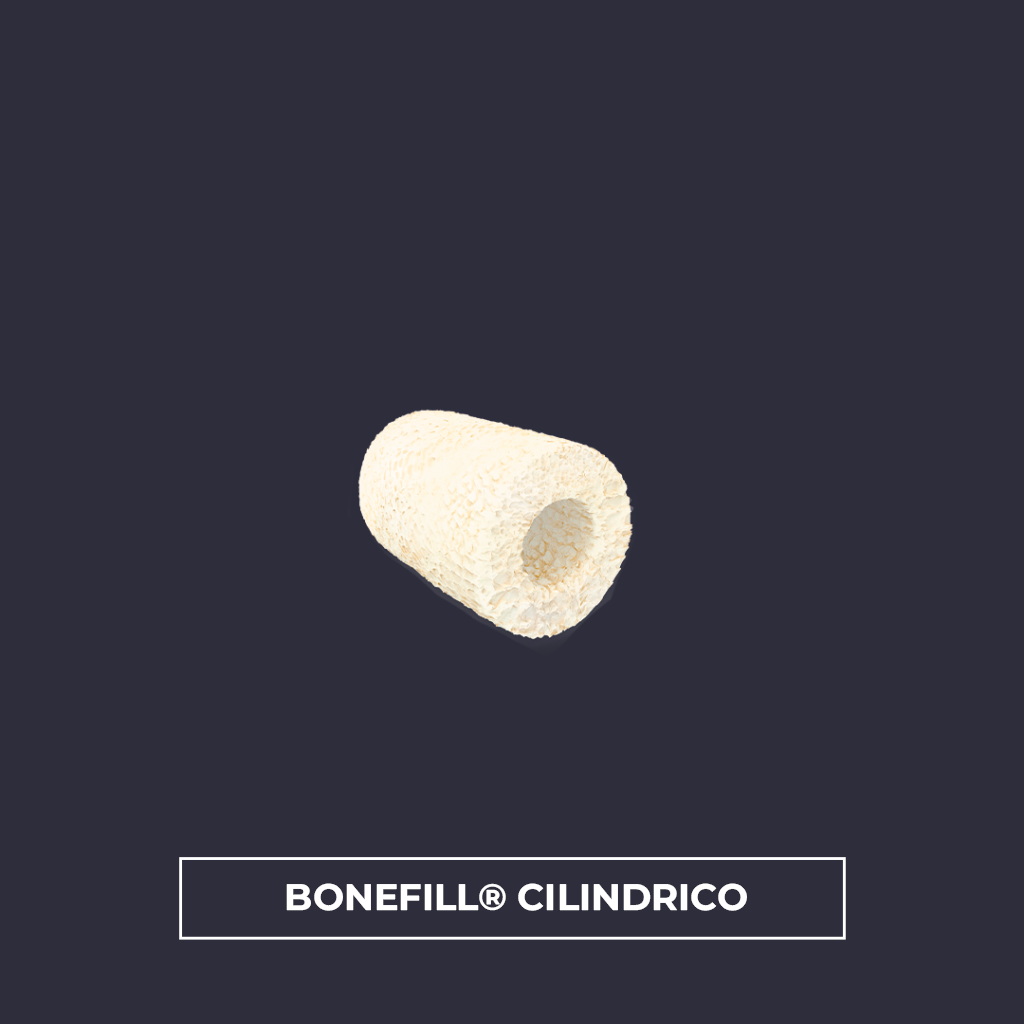

Bonefill® en forma de gránulos está disponible en los siguientes modelos: Bonefill® Dense, Bonefill® Mix y Bonefill® Porous . En forma estructural , está disponible en los siguientes modelos: Bonefill® Cortical Sheet, Bonefill® Poroso , Poroso Cylindrical y Bonefill® poroso pre-moldeado en una forma especial .